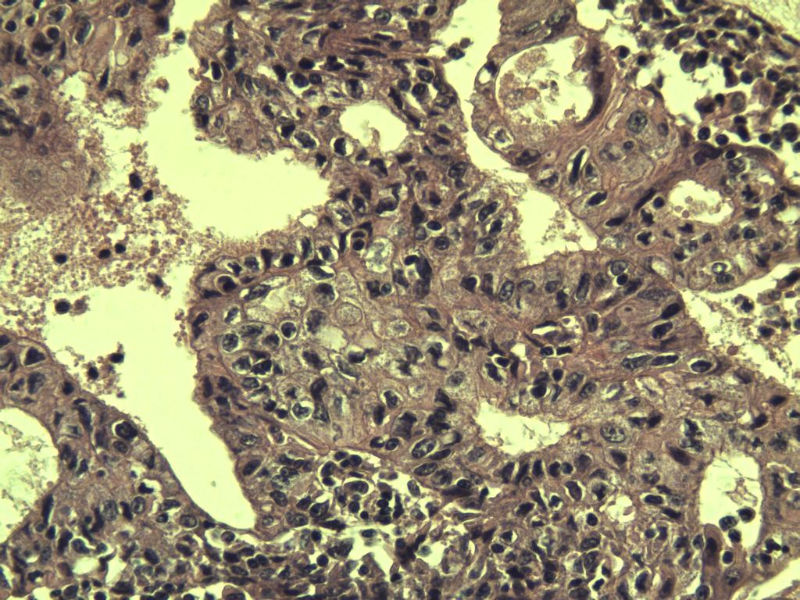

女,57岁,全切子宫一个,宫体体积 9 × 8 × 7 cm3,肌壁厚 2.5 cm,内膜菲薄,部分区域增厚达 0.4 cm(约3*2.5cm区域)。 请问各位老师 这个可以诊断子宫内膜癌了吧? 深肌层没有看到浸润。

患者因"发现下腹部包块1月多"入院 宫体体积 9 × 8 × 7 cm3,肌壁厚 2.5 cm,内膜菲薄,部分区域厚 0.4 cm(约3*2.5cm)。宫颈结构不清,长约 2.5 cm,表面欠光滑。临床诊断宫颈宫腔积液.